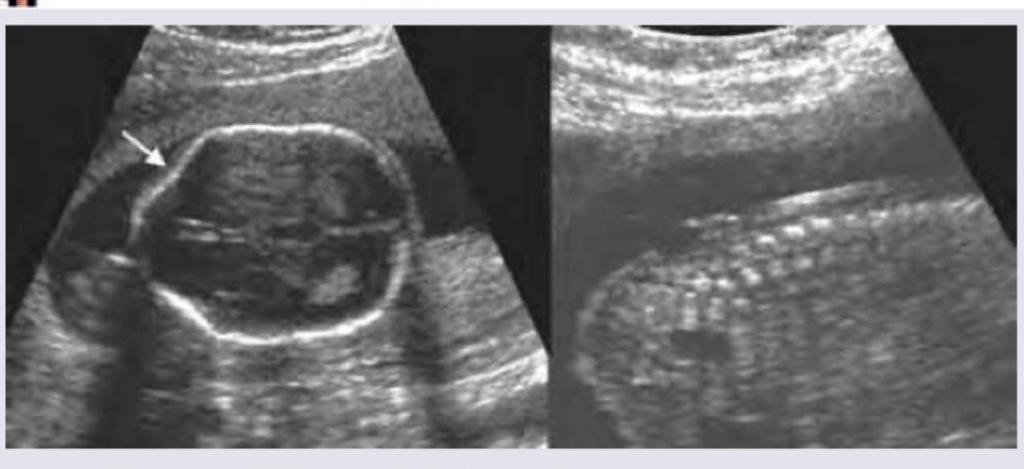

Keyhole sign on fetal ultrasound is seen in:

Explanation: ***Dandy-Walker syndrome*** - The ultrasound image shows **enlargement of the posterior fossa** with a **large cyst occupying the space normally taken by the cerebellum**, and a **keyhole sign** (arrow pointing to a defect where the cerebellar vermis should be). This is characteristic of Dandy-Walker syndrome. - Absence or **hypoplasia of the cerebellar vermis** is a hallmark feature, leading to communication of the fourth ventricle with a posterior fossa cyst. *Arnold-Chiari malformation* - Characterized by **herniation of cerebellar tonsils** through the foramen magnum and often associated with myelomeningocele. - Key ultrasound findings include a **lemon sign** (flattened frontal bones) and **banana sign** (anteriorly curved cerebellum), which are not depicted here. *Spina bifida* - This is a **neural tube defect** involving incomplete closure of the spinal column. - While it can be associated with Arnold-Chiari malformation, the primary features of spina bifida (e.g., a **sacral defect** with a mass) are not shown in these images. *Aqueductal stenosis* - Results in **dilation of the lateral and third ventricles** due to obstruction of cerebrospinal fluid flow in the aqueduct of Sylvius. - It primarily affects the supratentorial ventricular system and does not typically involve the **posterior fossa cyst** and **vermic hypoplasia** seen in the image.